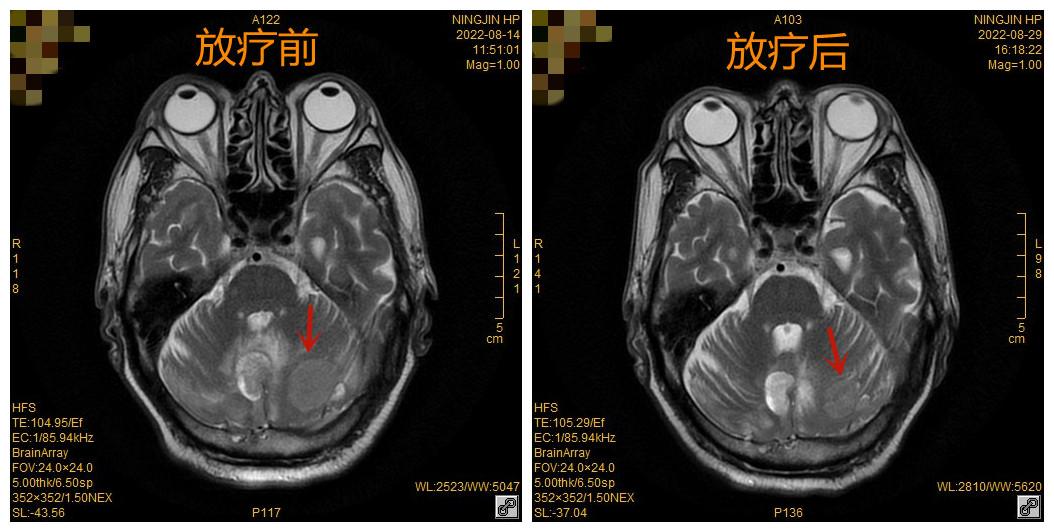

1个月前,董某某出现头痛、头晕等症状,经查头颅MRI提示:颅内多发占位病变,考虑转移瘤。

因董某某颅内存在多发转移瘤,放疗科主任赵恒西决定给予患者全脑放疗,即放疗剂量采用常规分割30Gy分10次进行,2周完成。经过放疗科团队精确定位、精确计划、精确治疗之后,患者在放疗过程中未出现特殊不适,放疗结束后复查MR颅内多发转移瘤较前均明显缩小,放疗效果明显。